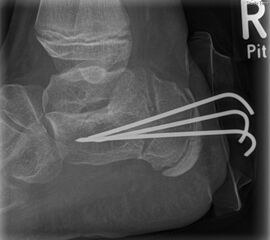

Zusätzlich schränken Wachstumsfugen die Wahl der Osteosynthese ein. Eine die Fuge kreuzende Osteosynthese ist ausschließlich mit Kirschner-Drähten möglich (Abb. 3).

Abb. 3 a-j: Beispiel einer Calcaneusverschiebeosteotomie mit offenen Wachstumsfugen und der entsprechenden Osteosynthese mit Kirschner Drähten. Lokalisation der Osteotomie (a), Lage der Fräse (b-d), Drahtlage mehrere Ansichten (e-h), Heilung der Osteotomie 4 Wochen postoperativ und Entfernung der Drähte (i-j).

Zum Lesen der Bildbeschreibung und zur Vollansicht bitte die Bilder anklicken. Bilder: A. Helmers.